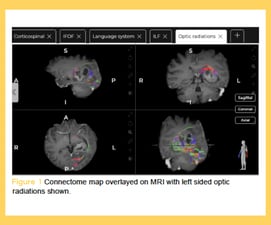

Improved Post-Operative Status: Preoperative connectomic analysis using Quicktome, visualizing both traditionally eloquent and higher cognitive networks, was associated with a significantly greater improvement in post-operative mRS scores at first follow-up for intra-axial tumor patients compared to those treated without connectomic analysis. This suggests that a surgical approach informed by a patient's unique connectome, not just traditional anatomy, leads to better functional preservation.

(MIPS) for brain tumors, using tubular retractors and pre-operative connectomic analysis with Quicktome, was associated with a 0% rate of postoperative neurologic deficits compared to 43.8% in the traditional control group. The data suggests this approach optimizes functional preservation and promotes postoperative neuroplasticity, reinforcing the role of connectomics in surgical safety.

An Alternative to Awake Craniotomy: A pilot study comparing awake craniotomy with connectome-guided resection under general anesthesia for language-eloquent gliomas found the latter to be a viable alternative when awake craniotomy is contraindicated. While awake craniotomy remains the gold standard, language, motor, and KPS preservation was comparable between the two groups.

Enhancing Global Network Integrity: Structural and functional connectomics allow for the quantitative assessment of changes in large-scale brain network connectivity post-resection. Improvements in tract-level symmetry and Fractional Anisotropy (FA) suggest the potential for not only preserving but also enhancing global network integrity. This further supports a personalized, connectome-informed definition of eloquence.

Pre- and Post-operative Functional Connectome: One study utilized Quicktome to analyze pre- and post-operative functional connectome changes in a vestibular schwannoma (VS) patient who experienced complete hearing loss. The analysis revealed that this post-operative hearing loss strongly correlated with the largest drop in the left language network's functional correlation and a significant increase in its network disruption.